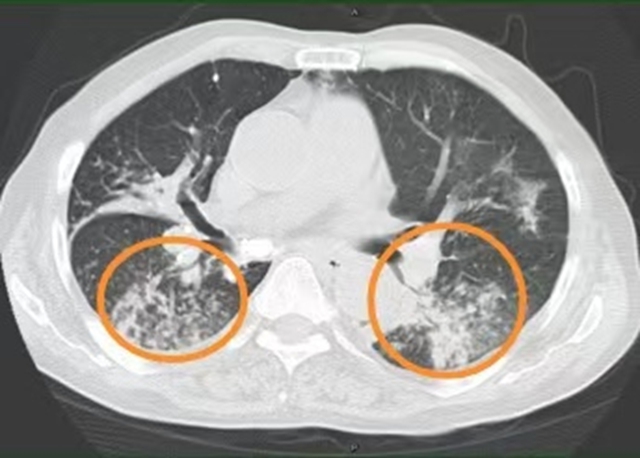

入院后,医生给王大爷用了抗感染、止咳化痰、营养支持等治疗,可3天过去,王大爷喘息、气促、咳嗽、咯黄痰仍没缓解,胸壁包块也没缩小,包块局部触摸还有波动感。复查胸部CT提示:双肺多发结节影、磨玻璃影、斑片影,部分见肺实变影,部分支气管牵拉扩张,左肺下叶部分支气管闭塞。

“终于找到凶手了!”敖素华教授立刻调整治疗方案,用上了针对诺卡菌的抗生素。用药1周后,王大爷的咳嗽明显减轻,黄痰减少,胸壁的包块慢慢缩小,2周后复查CT提示双肺炎症减少。